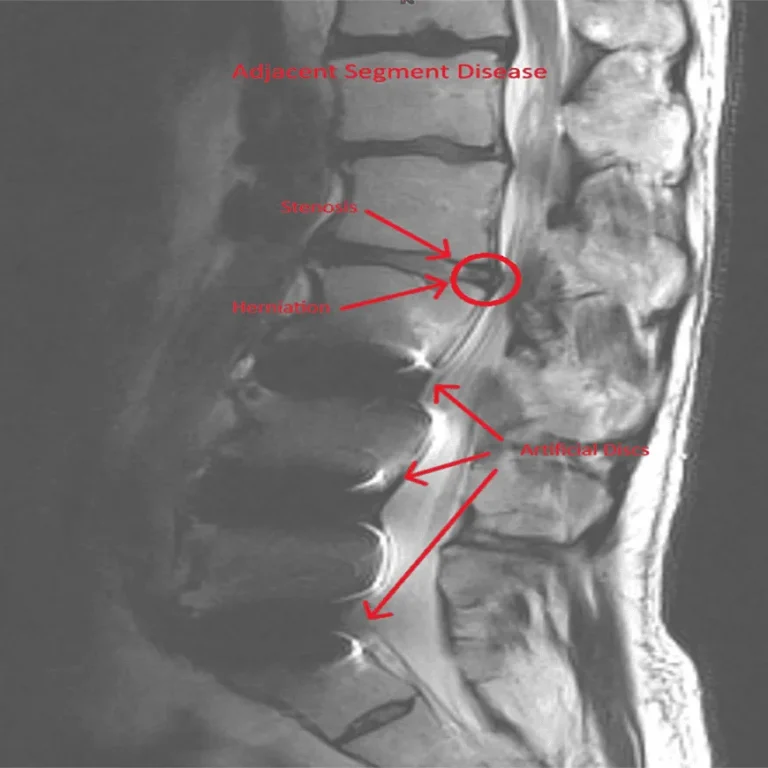

Annotated spinal MRI showing herniation, stenosis, and artificial discs with "Adjacent Segment Disease" label.

6) Adjacent Segment Disease

Adjacent segment disease is common after laminectomy and requires additional surgery.

7) Stenosis Persists or Returns

Stenosis either persists or reoccurs commonly after laminectomy and will require additional surgery such as Fusion.